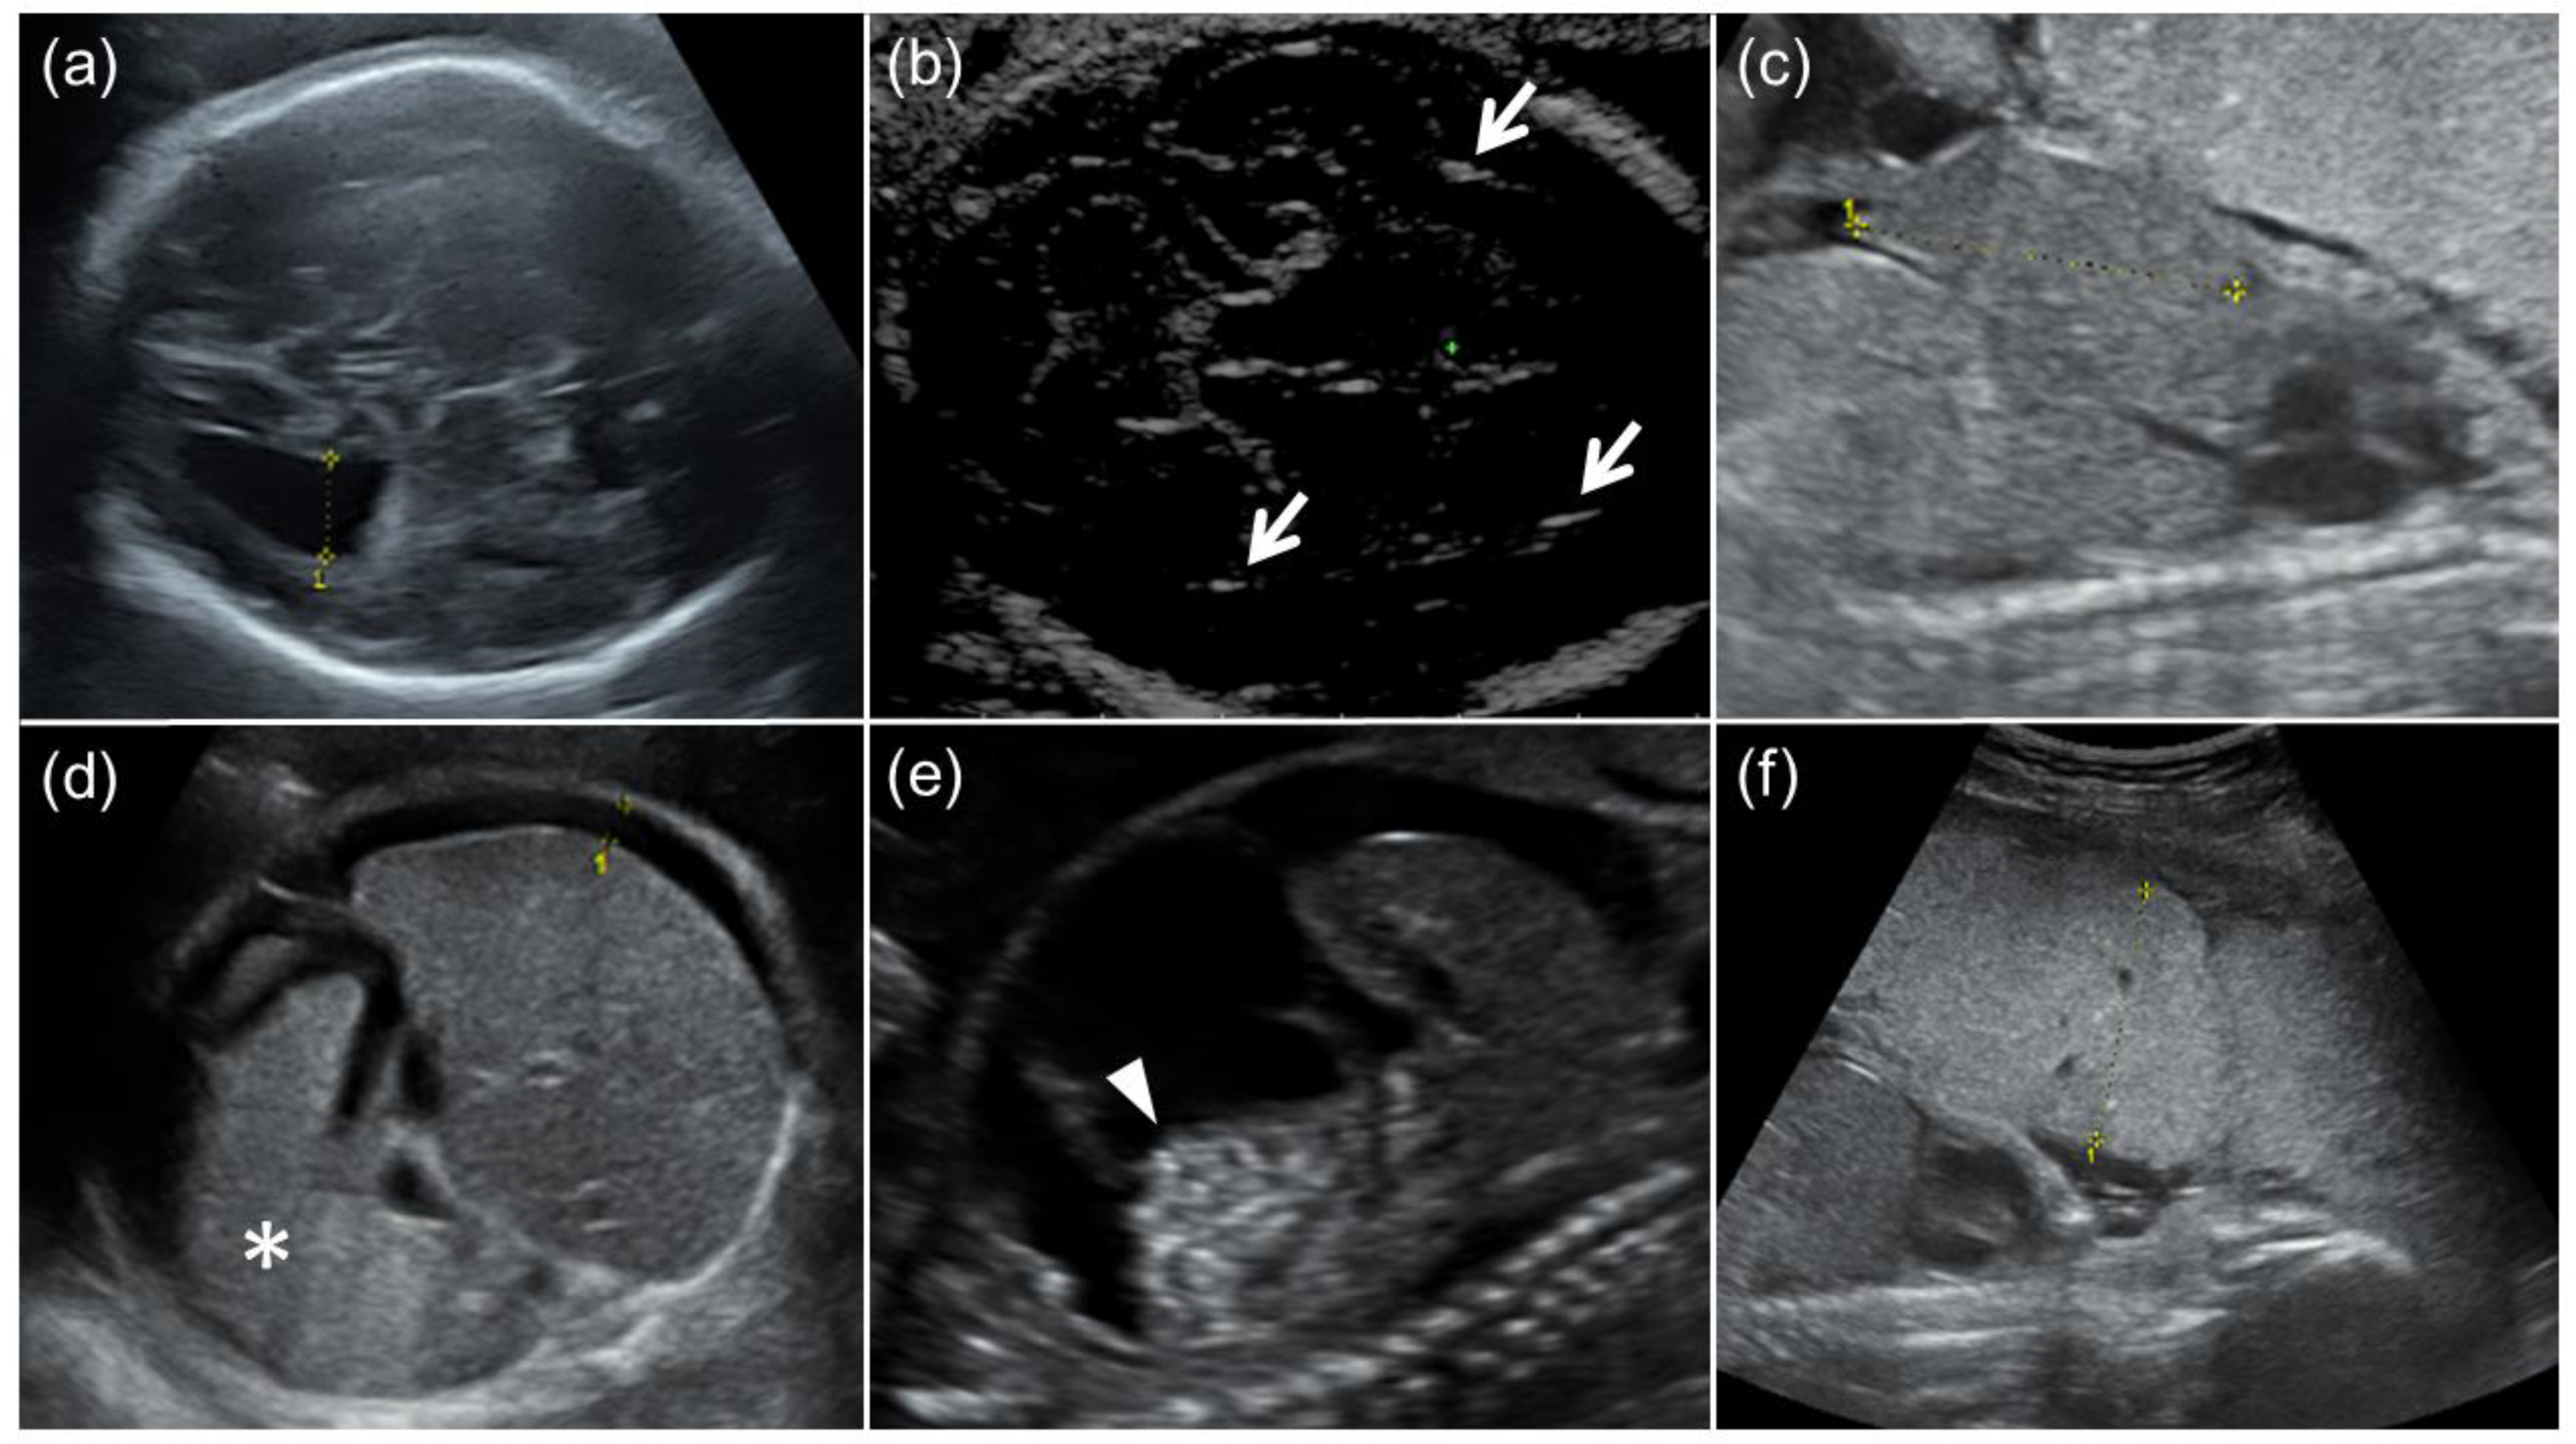

This retrospective cohort study was approved by the Institutional Review Board of Kobe University Hospital (Reference Number 928). Fetuses delivered at the university hospital who were prenatally diagnosed with symptomatic cCMV through imaging findings associated with cCMV and positive amniotic fluid CMV-DNA PCR were included. Fetuses in pregnancies that ended in induced abortion or those delivered at other hospitals were excluded. Eighteen fetuses who were prenatally diagnosed with symptomatic cCMV between October 2009 and October 2022 were enrolled. All fetuses underwent detailed US examinations for the detection or follow-up of imaging findings associated with cCMV at least once a week. The following US findings in fetuses and placentas were defined as imaging findings associated with cCMV, as follows: FGR, ventriculomegaly, intracranial calcification, cysts or pseudocysts in the brain, microcephaly, ascites, hepatomegaly, splenomegaly, hyperechoic bowel, and placentomegaly (Figure 1). The US examinations were performed by perinatologists (K.T., M.U., and S.T.) using the Voluson E8 or E10 (GE Healthcare, Milwaukee, WI, USA) or the ARIETTA 60 (Hitachi Aloka Medical, Tokyo, Japan). FGR was defined as an estimated fetal body weight (EFBW) ≤ the 3rd percentile for gestational weeks (GW) [18,19]. Microcephaly was defined as a head circumference (HC) ≤ the mean −3.0 SD for GW [20]. Ventriculomegaly was defined as a lateral ventricular atrial diameter ≥ 10 mm, and classified into three categories: mild (10–12 mm), moderate (12–15 mm), or severe (≥15 mm) [21]. Hepatomegaly and splenomegaly were defined as biometric measurements of the fetal liver and spleen beyond the 95% confidence interval (CI) of the reference values for GW, respectively [22,23]. Placentomegaly was defined as a placenta thickness ≥4 cm in the second trimester or ≥6 cm in the third trimester [24,25].

Figure 1. Fetal ultrasound findings of congenital cytomegalovirus (CMV) infection. (a) Moderate ventriculomegaly. The lateral ventricular atrial diameter at 31 GW was 1.3 cm. (b) Arrows indicate intracranial calcification. (c) Hepatomegaly. The fetal liver length at 24 GW was 4.2 cm (the reference value for 24 GW: ≤3.8 cm). (d) Splenomegaly and fetal ascites. An asterisk indicates enlarged fetal spleen, and the width of fetal ascites around the fetal liver was 0.8 cm. (e) Fetal ascites and hyperechoic bowel (arrowhead). (f) Placentomegaly. The placental thickness at 24 GW was 5.1 cm.